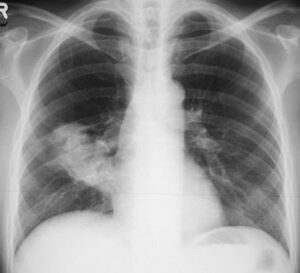

Tumore polmonare